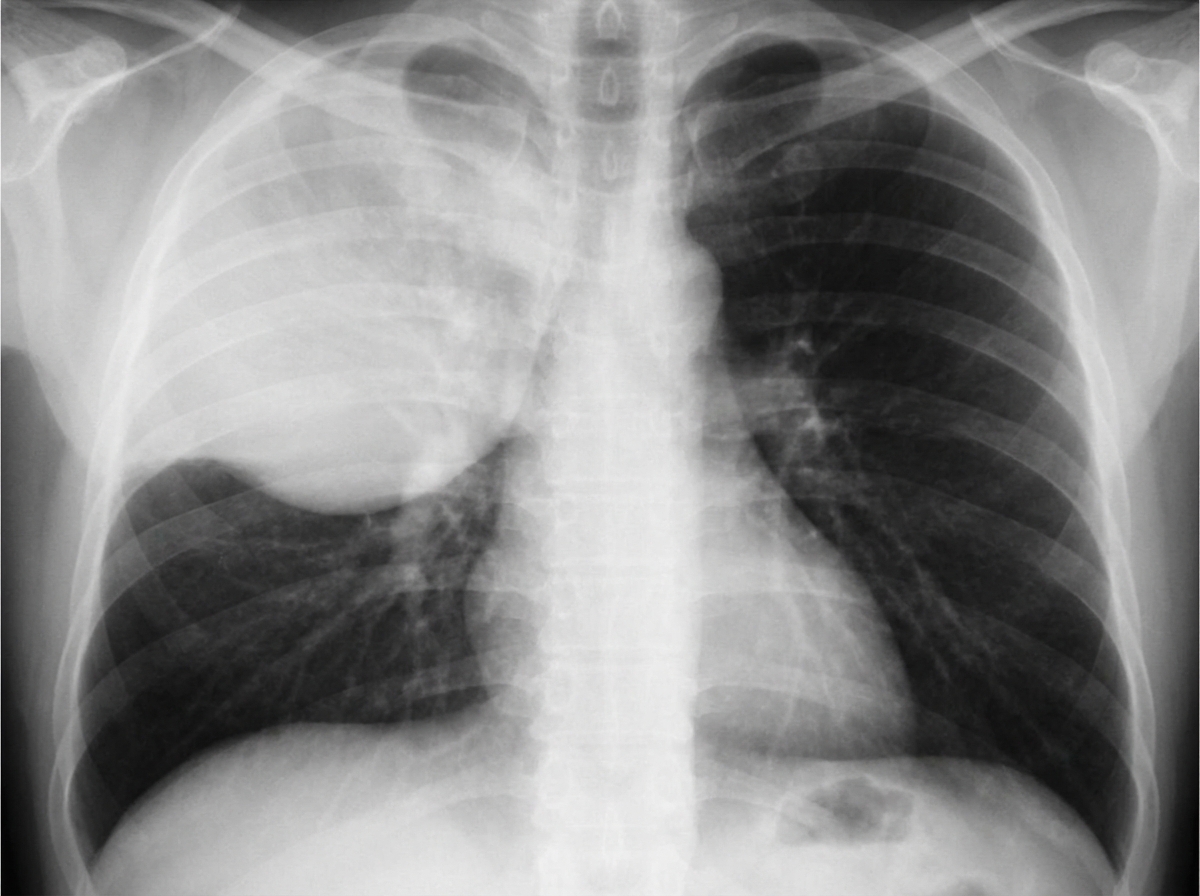

A 34-year-old woman is admitted with a history of fever, chills, and greenish sputum for 10 days. She has a history of alcohol and substance abuse. On physical examination, vital signs are: pulse 113 bpm; temperature 101degF; respirations 25/min; blood pressure 110/78 mm Hg. She appears ill and has crackles with egophony and E to A changes in the right upper lung field. Laboratory data: Hb 12 g/dL; Hct 37%; WBCs 15.0/uL; differential BUN 48 mg/dL; creatinine 1.7 mg/dL. Chest radiographs are shown. What is the most likely diagnosis?

Explanation: ***Klebsiella pneumonia*** - The combination of **alcohol abuse**, **right upper lobe consolidation** with **bulging fissure sign**, and **greenish sputum** are classic for Klebsiella pneumoniae. - **Elevated WBC count** (15.0/uL) and **systemic toxicity** with fever and chills support acute bacterial pneumonia, particularly in immunocompromised patients. *Loculated empyema* - Would typically show **pleural fluid collection** with **loculations** on imaging, not consolidation with bulging fissure. - Usually presents with **persistent fever** despite antibiotic treatment and requires **drainage procedures** rather than just antimicrobial therapy. *Postobstructive pneumonia* - Typically occurs **distal to bronchial obstruction** by tumor, foreign body, or mucus plugs, more common in **elderly patients**. - Would expect **atelectasis** with consolidation and possible **mediastinal shift**, not the bulging fissure pattern seen here. *Tuberculosis* - Usually presents with **chronic symptoms** over weeks to months, not acute 10-day illness with high fever. - Typically affects **upper lobes** but shows **cavitation** and **fibronodular changes** rather than acute consolidation with bulging fissure.